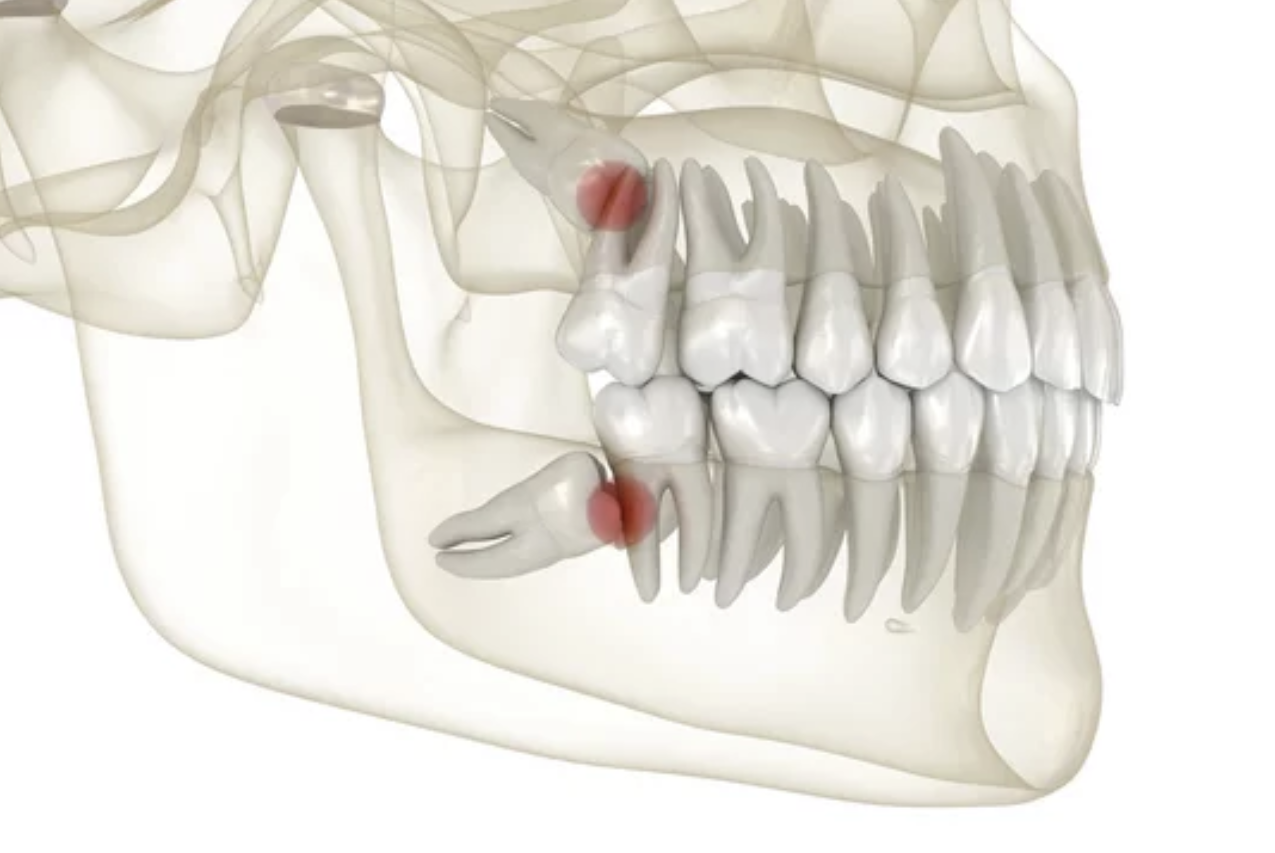

사랑니는 구강 내에 가장 안쪽에서 맹출하는 세번째 큰 어금니(제3대구치) 입니다.

영구치 중에서 가장 늦게 맹출하는 치아로, 보통 10대 후반에서 20대 초반에 나타납니다. 구강 내 공간이 부족한 경우 사랑니는 제대로 위치하지 못하거나 매복되는 경우가 있습니다. 이런 사랑니의 경우 주변 치아의 손상을 일으키거나 주변 잇몸의 통증, 염증의 원인이 될 수 있는데, 이런 경우 사랑니 발치가 필요할 수 있습니다.